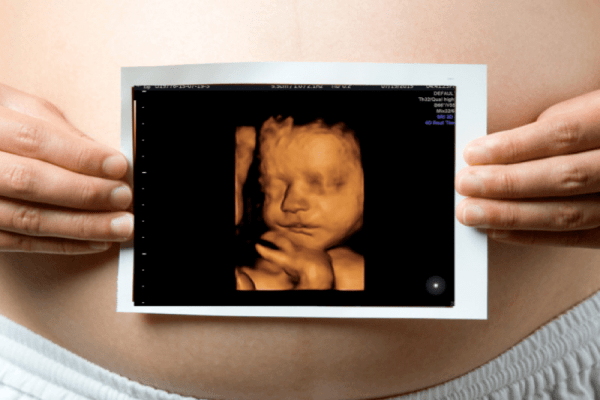

3D/4D Ultrasound in PCMC

Advanced imaging that provides a realistic view of the fetus. Preferred for detailed prenatal assessment and bonding with your unborn baby.